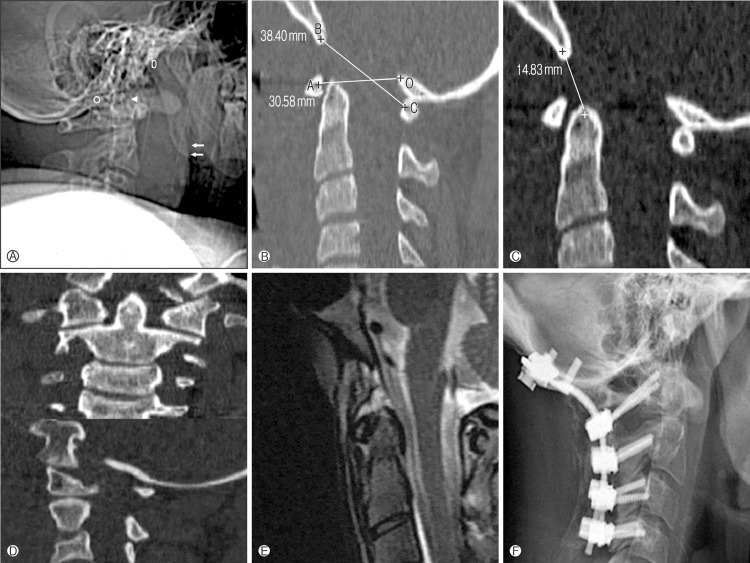

From: Kim et al Korean Journal of Spine 2012

- majority survivors treated with occipito-cervical fusion

Reduction and Halo-Thoracic Brace (HTB)

Reduce in OT

- image intensifier

- putting sandbags under thorax

- allows head to reduce posteriorly

- assess with image intensifier

- apply halo vest

- add compression

HTB 3 months

- assess stabilty with flexion / extension views

Surgical stabilization

Occipito-cervical fusion